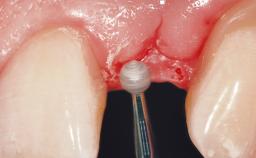

Late Placement of an Implant in a Maxillary Left Central Incisor Site

A 36-year-old female patient was referred for the replacement of the upper left central incisor (tooth 21), which had fractured. Although the tooth had been asymptomatic for many years, the crown began to loosen, at which time she presented to her dentist for an assessment. Teeth 21 and 22 had both been endodontically treated many years previously. She was a healthy individual and a non-smoker.

Soft Tissue Grafting Simultaneous

Soft Tissue Contour and Volume Slightly compromised